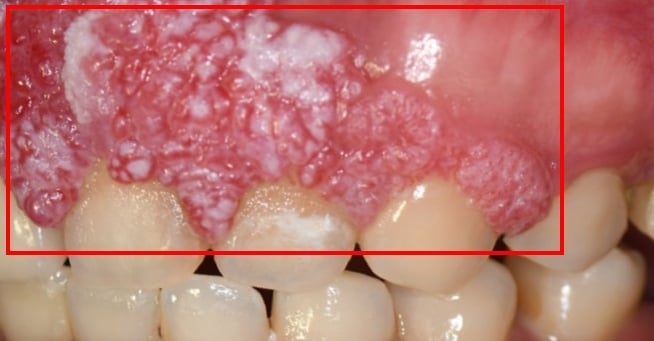

▲患者病灶位於上顎齒齦區域。(圖/中山附醫提供)

邱昱瑋醫師也表示,不像肺癌或肝癌等癌症,口腔癌多數有明顯的口腔異常症狀、相對容易被發現,但臨床發現不少患者直到症狀惡化嚴重才求醫、確診時已是晚期,導致錯失早期治療時機。與一般口腔潰瘍或牙周病不同,若發現口腔潰瘍超過兩週未癒、傷口呈現糜爛狀、容易出血,或病灶可能呈不規則突起、類似菜花,應儘早就醫檢查。